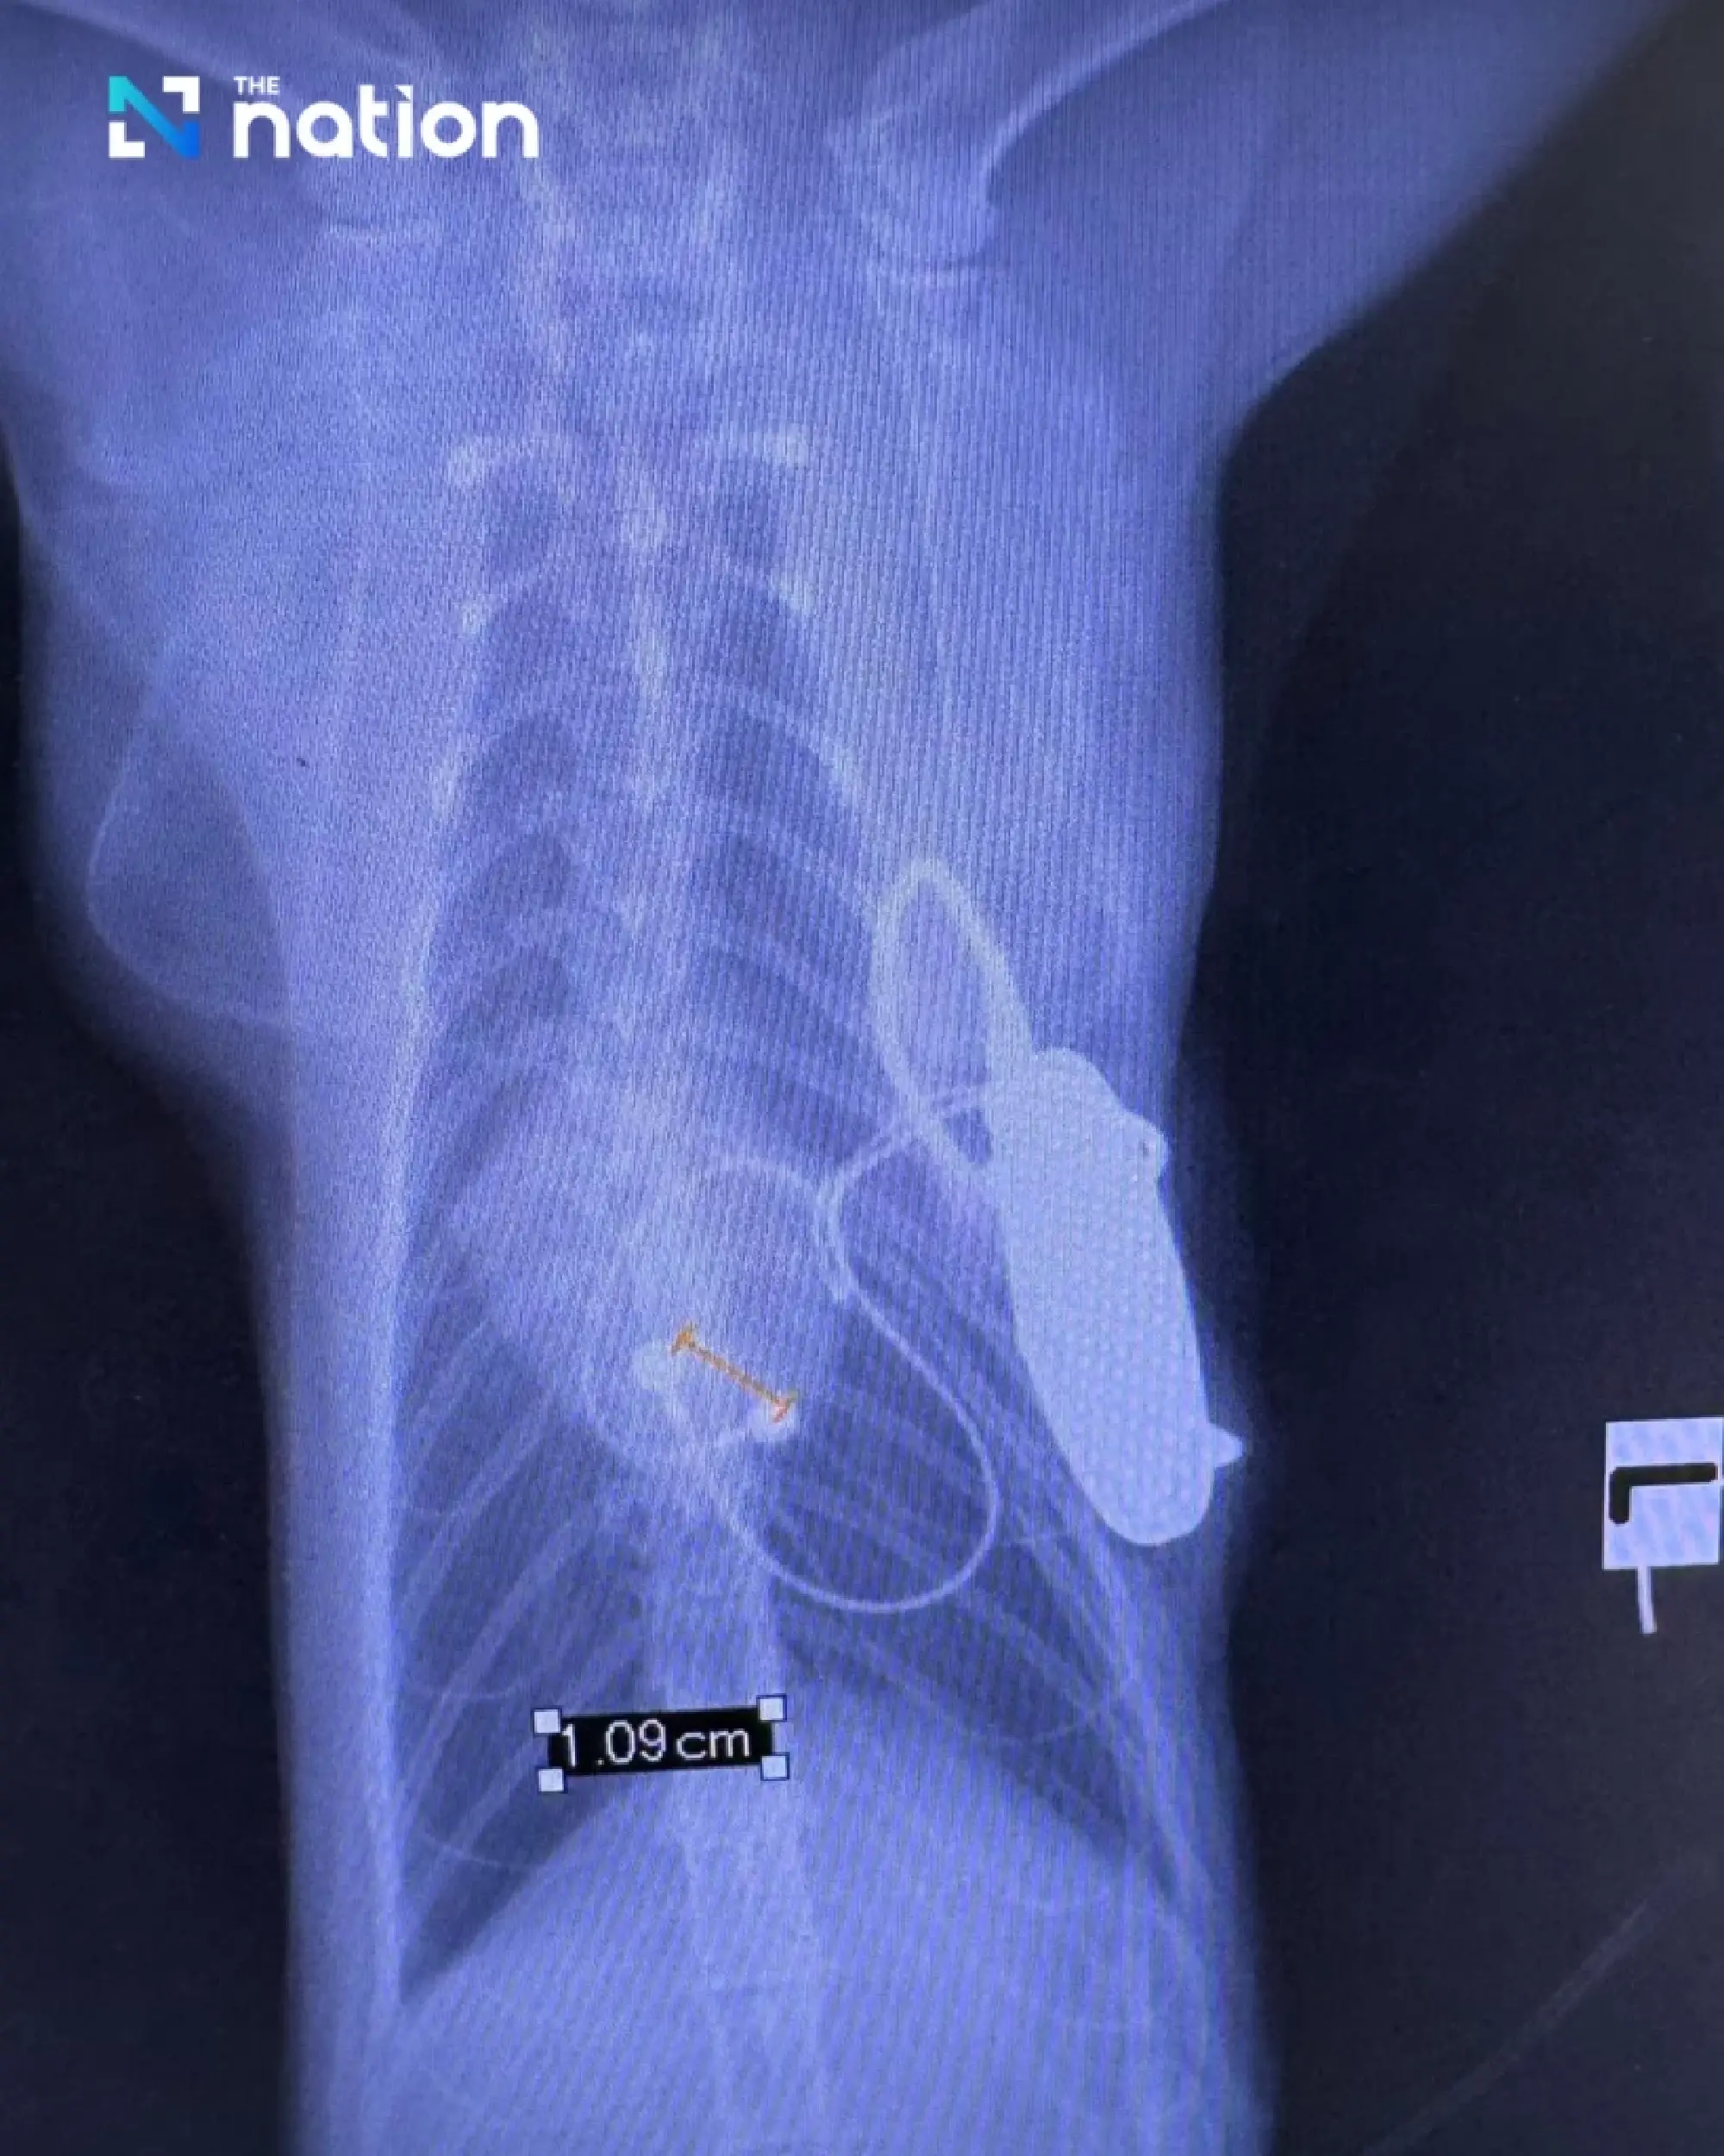

Implanting a pacemaker in a cat presented considerable surgical obstacles. Unlike dogs, whose larger veins allow the pacemaker lead to be threaded through the neck, cats have significantly smaller veins and thinner heart muscle walls — measuring just two millimetres — making the conventional approach too risky, as the lead could puncture the heart.

The surgical team instead opened the chest cavity between the ribs to access the heart directly, attaching the pacing lead to the heart's surface and implanting the small generator unit beneath the abdominal muscles.

The pacemaker device used in Pepsi's surgery is the same model deployed in human patients, fitted with appropriately sized leads. The unit itself costs around 45,000 baht, with the leads adding a further 10,000 baht.